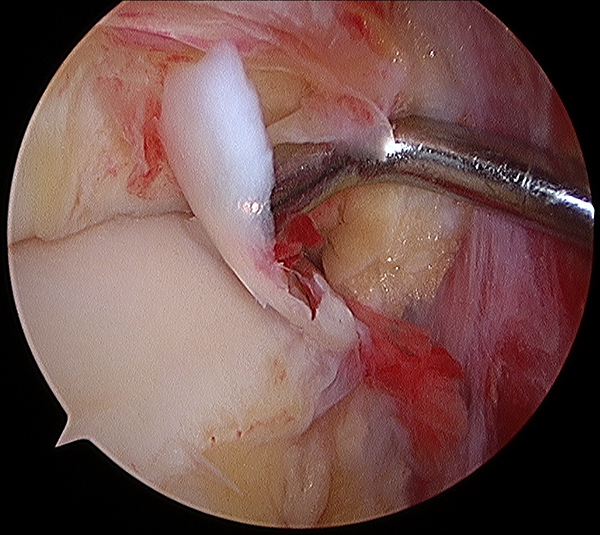

Todos fueron intervenidos quirúrgicamente por el mismo equipo quirúrgico con la metodología protocolizada que se realiza habitualmente en el centro. El procedimiento se realiza, con el paciente en decúbito dorsal, con anestesia raquídea, manguito hemostático colocado en la raíz del muslo, insuflado a 300 mmHg, lavado previo con clorhexidina y embrocado con alcohol ispropílico y clorhexidina. El primer tiempo es artroscópico, efectuado a través de los 2 portales clásicos antero-lateral y antero-medial, sin dispositivos de distracción. Se evalúa la articulación tibio-talar en busca de lesiones asociadas intra-articulares (fig. 1), y se evalúa la ruptura e inestabilidad de la sindesmosis (fig. 2). La diástasis se cuantifica en mm con el palpador (fig. 3). Se considera anormal un desplazamiento mayor a 2 mm. Se clasifica a la lesión como inestable cuando se logra ingresar con la óptica o con la punta del shaver en el espacio tibio-peróneo (abriendo la sindesmosis).

Figura 1: Visualización artroscópica de una lesión de la sindesmosis tibio-peronea inferior.